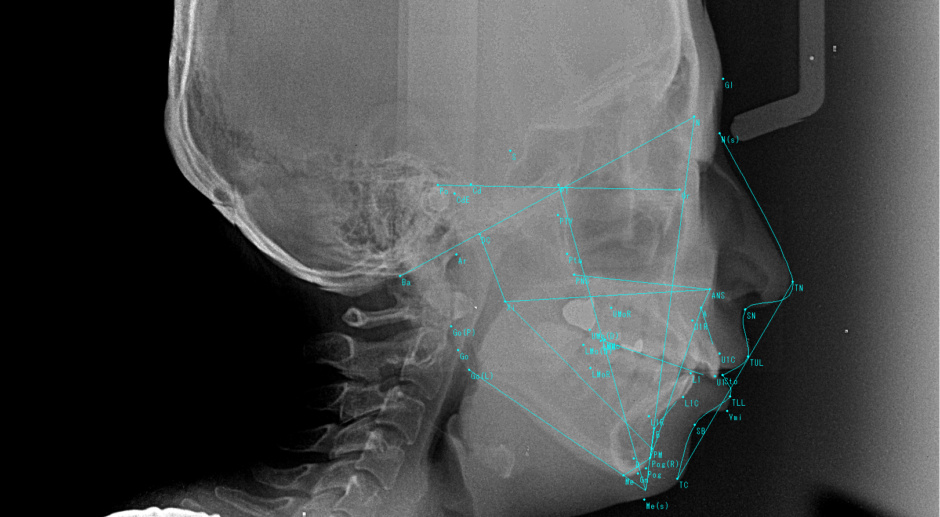

セファロ分析とは全世界で同じ規格で撮影するエックス線写真(レントゲン写真)を分析することを言います。

このエックス線写真(レントゲン写真)のことを、セファログラムと言います。

セファログラムは、側方頭部エックス線規格写真とも呼ばれます。

❝セファロ分析の計測点について❞

S・・・トルコ鞍の中心

N・・・鼻前頭縫合の前方限界点

Po・・・骨外耳道上縁点

Or・・・眼窩下縁でFHplaneに接する点

PNS・・・後鼻棘最後方点

ANS・・・前鼻棘の尖端

A・・・前鼻棘と上顎歯槽縁間の正中矢状断面上の最深部

Ar・・・下顎枝と後頭骨基底部下縁の交点

B・・・下顎結合部の全縁と下顎歯槽縁間の正中矢状断面上の最深点

Me・・・下顎結合部の正中矢状断面上の最下方点

Go・・・下顎下線平面と下顎枝口縁平面のなす角の2線が下顎角部と交わる点

Pog・・・下顎結合部最突出点

Gn・・・Facalplaneと下顎下縁平面のなす角の2線が下顎結合部で交わる点

U1・・・上顎中切歯の切縁

L1・・・下顎中切歯の切縁

Cd・・・下顎頭最上後方点

CdE・・・下顎頭最後方点

Ba・・・後頭骨の大後頭孔を形成する部分の前下縁

SN・・・鼻下点

これらの計測点は一部で、他にも様々な計測点があります。

❝セファロ分析における基準平面❞

SN平面・・・SとNを結んだ直線

FH・・・OrとPoを結んだ直線

顔面平面・・・NとPogを結んだ直線

口蓋平面・・・ANSとPNSを結んだ直線

咬合平面・・・上下顎中切歯尖端の中点とMoを結んだ直線

下顎下縁平面・・・Meから下顎下縁に引いた接線

下顎後縁平面・・・Arから下顎角後縁部に引いた接線